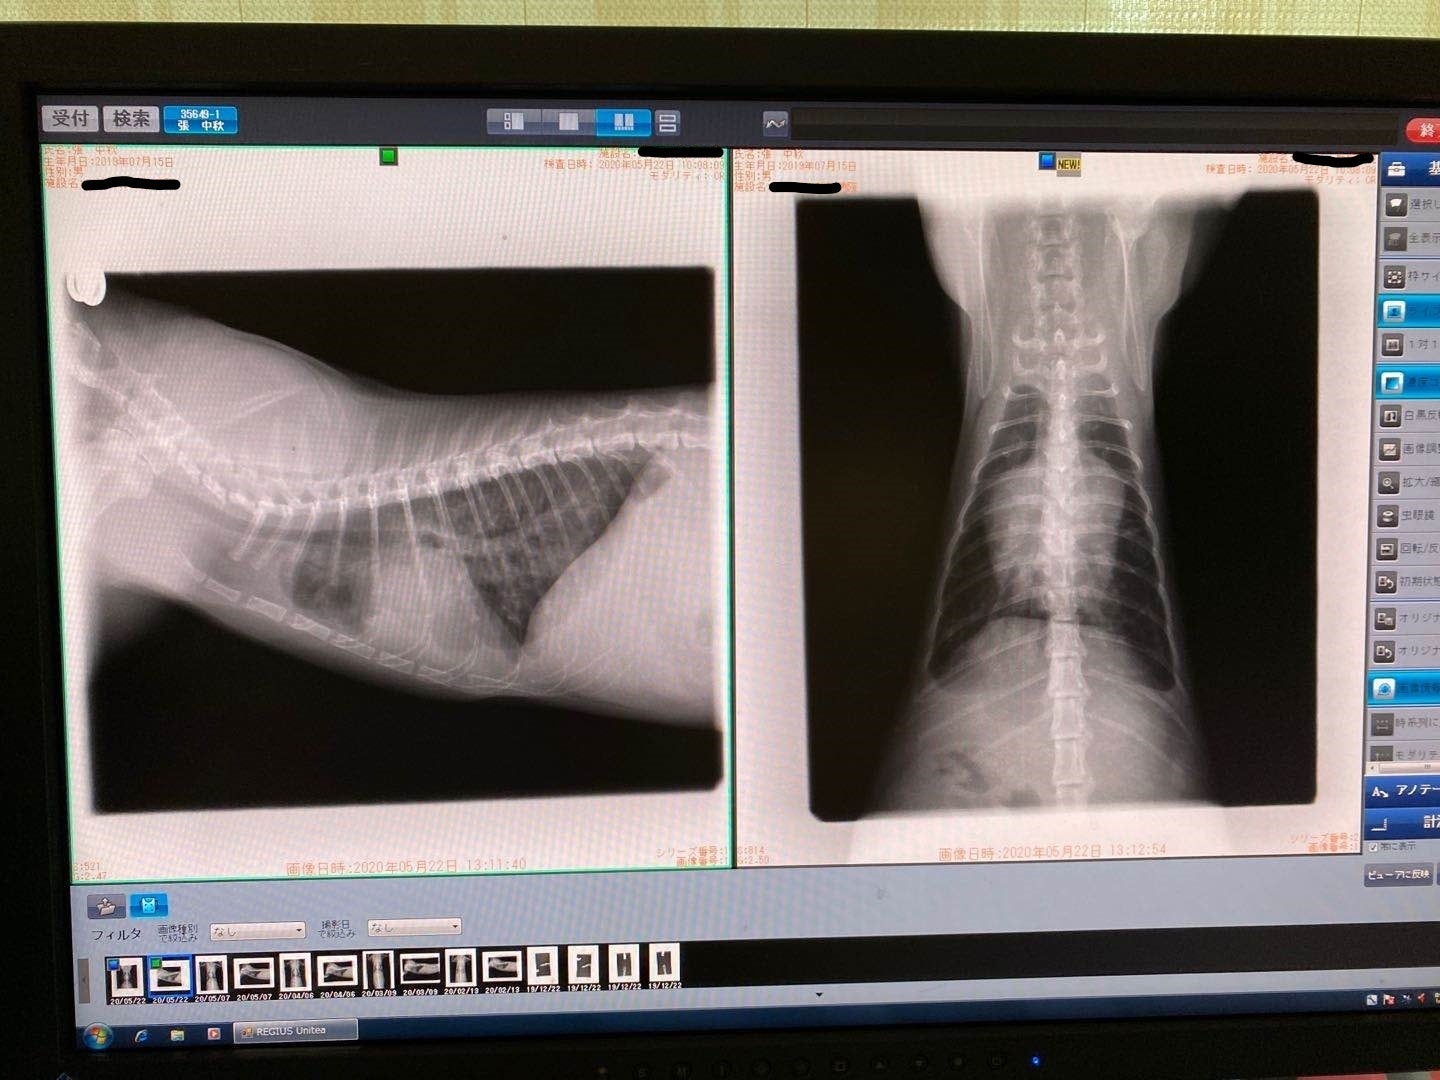

2/13去勢手術するため、身体検査をするとき、肺の中に薄い水影があって、念のため詳しい検査を行いました。

症状が軽い、判断が難しく、少し観察の時間が必要けど、最悪の場合はFIPを罹っているの可能性があると言われて、でも別の病気の可能性もあると言われました。3/9でレントゲン検査すると、水影が少し薄くになって、4月の検査も同じになって、FIPの可能性ではないかもと思います。けど、5月の検査はあまり変わらないになって、22日で急に発症になりました。前を振り返って見て、ずっと自分を責め続いている。

5/25家の近くの協力病院に行って、痛く辛い検査をして、中期混合型と診断されました。

腹水がたまっています

肉芽腫が見つかります

39℃の熱と重度の貧血もあります

強い炎症もあります